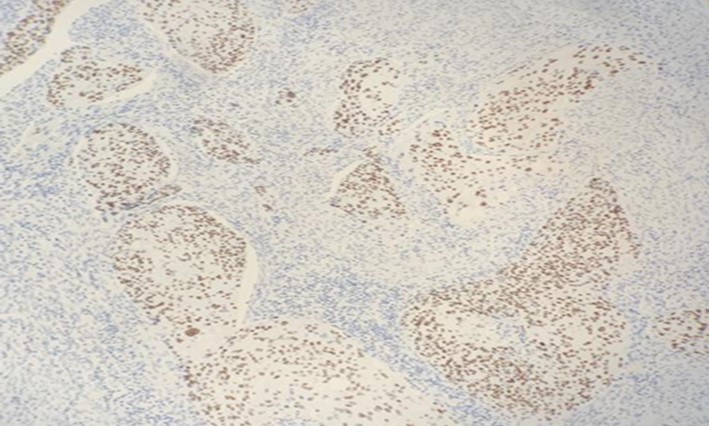

A 42-year-old gentleman, ex-smoker with underlying diabetes mellitus came to our clinic for right neck swelling for about 10 months. The swelling was gradually increasing in size and was giving occasional pain to the patient. But, there were no obstructive symptoms nor a history of prior exposure to radiation. Upon examination, there was a 2x2cm firm, fixed and non-tender swelling palpable at level II of right neck, with no skin changes seen. The facial nerve was intact and the oral cavity was clear. Proceed with flexible scope, there was no mass seen, and laryngeal structures were normal. Fine needle aspiration revealed normal salivary gland elements. A contrasted-CT scan reported a deep lobe parotid gland mass with non-opacification of the right internal jugular vein which could be from compression or thrombosis. [Figure 3] A wedge biopsy was performed subsequently which reported as squamous cell carcinoma, moderately-differentiated. [Figure 4, Figure 5 & Figure 6] Given the malignancy reported, a right total parotidectomy with right selective neck dissection was performed. Post-operatively, the patient developed House-Brackmann grade II facial nerve palsy. Histopathology showed evidence of squamous cell carcinoma with no involvement of adjacent nodes. A final diagnosis of T3N0M0 squamous cell carcinoma of the parotid gland was established. The patient was then referred to the oncology team for chemoradiation. Currently, the patient has completed adjuvant radiotherapy with no signs of recurrence observed so far at six months follow-up.

Figure 6.Photomicrograph show positivity to immunohistochemistry marker p40(nuclear) in SCC of parotid (x20 high power field)